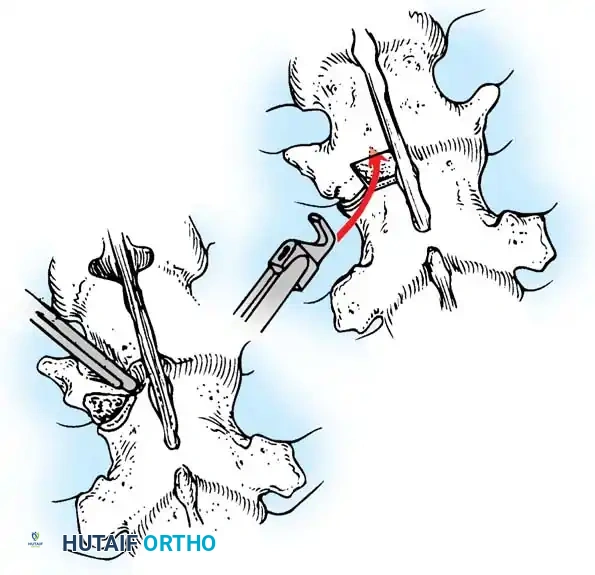

The Moe Technique (Thoracic Spine)

The Moe technique is a highly effective method for achieving intra-articular arthrodesis in the coronally oriented thoracic facet joints.

Fig. 38-26: The Moe technique of thoracic facet fusion, demonstrating the creation of hinged bone flaps.

- Expose the spine fully to the tips of the transverse processes.

- Using a sharp osteotome or Cobb gouge, begin a cut over the cephalad articular process at the base of the lamina.

- Carry this cut along the transverse process almost to its tip. Bend this cortical fragment laterally so it lies between the transverse processes, ideally leaving it hinged on its lateral periosteal attachment to preserve local vascularity.

- Thoroughly denude all articular cartilage from the superior articular process using a sharp curet.

- Make a secondary cut in the superior articular facet, working medially to laterally, producing another hinged fragment.

- Pack the resulting intra-articular defect tightly with cancellous bone graft.